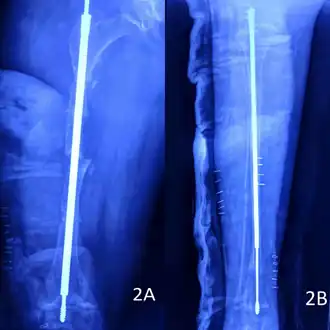

Metal rods can be surgically inserted in the long bones to improve strength, a procedure developed by Harold A. Sofield when he was Chief of Staff at Chicago's Shriners Hospitals for Children, a hospital that offers orthopedic care and surgery to children regardless of their family's ability to pay.[115] Large numbers of children with OI came to Shriners, and Sofield experimented with various methods to strengthen their bones.[116] In 1959, with Edward A. Millar [sic], Sofield wrote a seminal article describing a three-part surgery that seemed radical at the time: precisely breaking the bones ("fragmentation"), putting the resulting bone fragments in a straight line ("realignment"), then placing metal rods into the intramedullary canals of the long bones to stabilize and strengthen them ("rod fixation").[117] His treatment proved useful for increasing the mobility of people with OI, and it has been adopted throughout the world—it became standard surgical treatment for severe OI by 1979, in which year David Sillence found that ≈2⁄3 of the patients he surveyed with OI type III had undergone at least one rodding surgery.[42]: 108

In those with type III OI who had undergone rodding surgery, 79.5% had the femurs and tibias of both legs rodded.[25]: Table I The most common form of rods used are intramedullary (IM) rods, some of which, such as the Fassier–Duval IM rod, are telescoping, meaning that they are designed to grow as the child grows, in an attempt to avoid the necessity of revision surgeries.[118] Telescoping IM rods are widely used,[119] and the common Fassier–Duval IM rod is designed to be used to rod the femur, tibia, and humerus.[120]: 1 The surgery involves breaking the long bones in between one and three (or more)[119]: Figure 4 places, then fixing the rod alongside the bone to keep it straight.[120]: 11

While telescoping IM rods are intended to grow along with both the femur and tibia in developing children; surgeons have a preference to use non-telescoping IM rods, such as Rush rods, in the tibia, which grows less comparatively—the JB&JS review found that while 69.7% of femurs were treated with telescoping IM rods, only 36.9% of tibiae were.[25]: Table IV